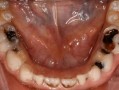

(图片来源网络,侵删)